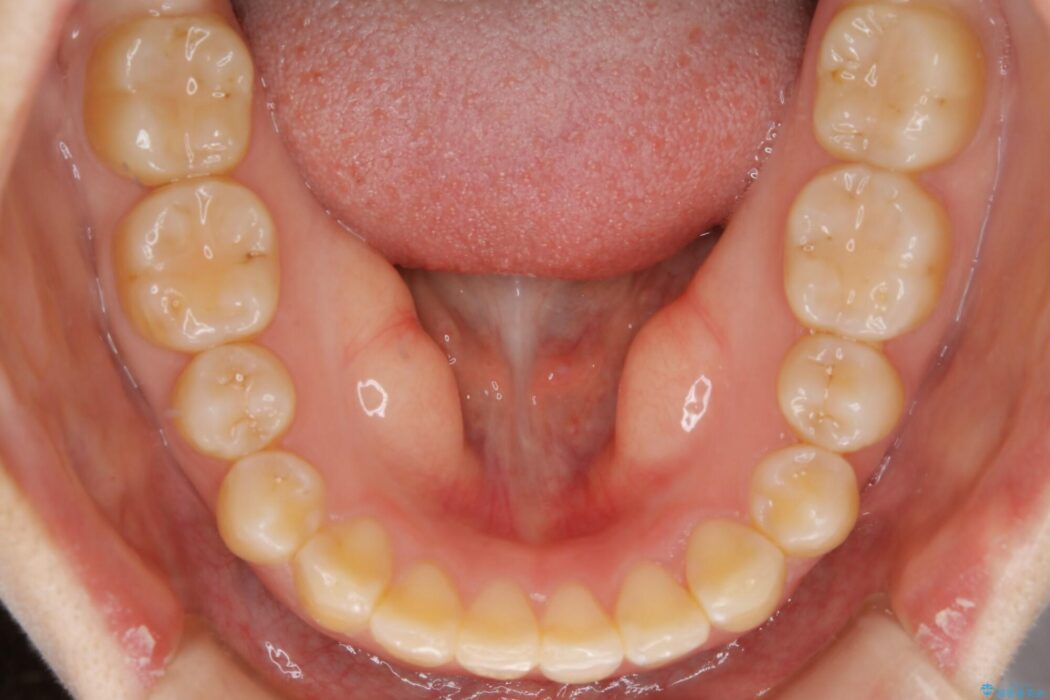

治療後について

咬合調整は咬合力を複数の歯に均等に分散することで歯の負担を少なくでき、歯の長持ちに繋がります。

噛み合わせが改善されたことによりしっかり噛めるようになったと喜んでいただきました。